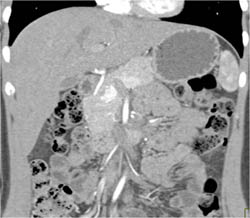

Diagnosis

Pancreatitis